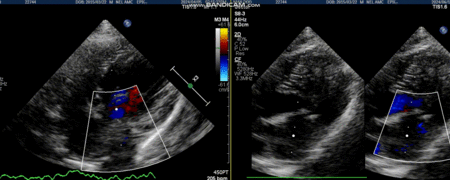

심정지까지 이루어지면 좌심방을 절개하고 들어가 판막과 건삭 상태를 확인한다. 이때 수술자는 건삭파열의 위치 및 판막의 퇴행성 변화를 확인하고 적절한 수술 방법을 선택하여 이첨판막 재건술을 실시한다. 판막 기능의 수복이 완료되면 심장을 다시 뛰게 하고 체외순환기의 역할을 줄이는 weaning 과정을 거친다. weaning 과정을 마치고 폐흉이 이루어지면 모든 수술 과정이 마무리된다.

수술 후 모든 환자는 이첨판 역류의 대부분이 소실되어 생리적 수준의 MR만이 남았으며, 모든 환자들은 수술 직후 이뇨제를 단약함과 동시에 심장 리모델링이 빠르게 진행되었다. 술 후 1주-1달 정도가 지나면 더 이상 피모벤단이 필요하지 않은 경우가 대부분이었다. 또한 환자들은 술 후 3개월이 지나면서 내복약을 복용하지 않게 되었고, 3개월이 지나지 않은 환자는 내복약을 중단하는 과정에 있다.